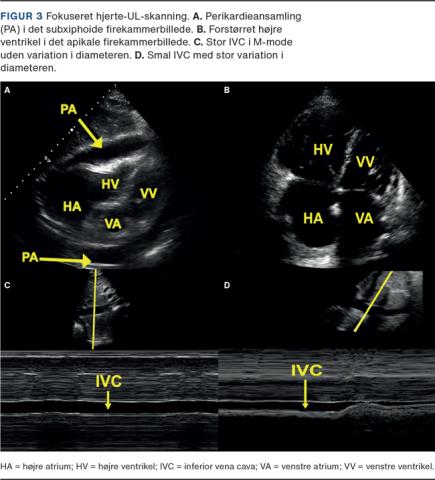

Fokuseret hjerte-UL-skanning (FoCUS) anvendes til at se tegn på perikardieansamling, højresidig belastning, nedsat venstresidig systolisk funktion og abnormal volumenstatus. FoCUS kan ikke erstatte ekkokardiografi og ændrer ikke ved indikationen herfor [10]. Ved FoCUS anvendes op til fem projektioner af hjertet (Figur 1B). Optimalt lejres patienten i rygleje til projektion af de subxiphoide vinduer og venstre sideleje til de øvrige projektioner.

Perikardieansamling vil erkendes som en anekkoisk bræmme omkring hjertet (Figur 3A) med høj sensitivitet og specificitet [11]. Ved hjertetamponade er ansamlingen hæmodynamisk betydende. Fund af perikardieansamling skal derfor altid ses i den kliniske kontekst og konfereres med relevante specialister.

Højresidig belastning vurderes med FoCUS ved at bedømme, om højre ventrikel er lige så stor eller større end venstre ventrikel (Figur 3B), hvilket er et indirekte tegn på forhøjet tryk i lungekredsløbet og bl.a. kan ses hos nogle patienter med lungeemboli, men også kan forekomme ved andre tilstande [12].

Inferior vena cava (IVC) visualiseres i længdesnit evt. med M-mode til bedømmelse af den respiratoriske diameterændring. I talrige studier har man undersøgt IVC’s betydning, og der er fortsat ingen konsensus [14, 15]. Akut anvendes bedømmelse af IVC i sine ekstremer og sammenholdes med de kliniske fund. En stor diameter og minimalt kollaps (Figur 3C) kan være foreneligt med forhøjet tryk i højre ventrikel og lungekredsløbet. Omvendt vil en smal IVC med stort kollaps (Figur 3D) kunne være foreneligt med hypovolæmi.